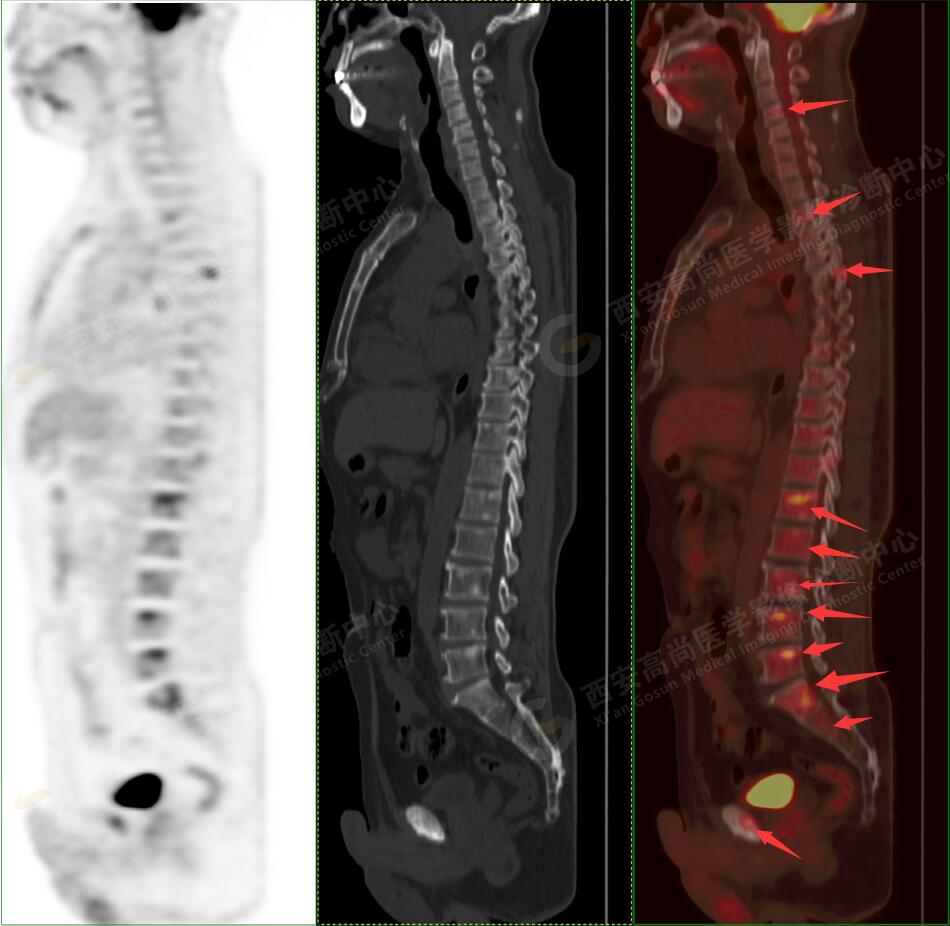

5.右側肱骨上段、左側肩胛骨、右側鎖骨胸骨端、胸骨、雙側多發(fā)肋骨、脊柱多發(fā)椎體及附件、雙側髂骨、雙側髖臼、雙側恥骨、雙側肱骨上段多發(fā)成骨性病變,呈不同程度FDG代謝異常增高,考慮為多發(fā)骨轉移瘤。